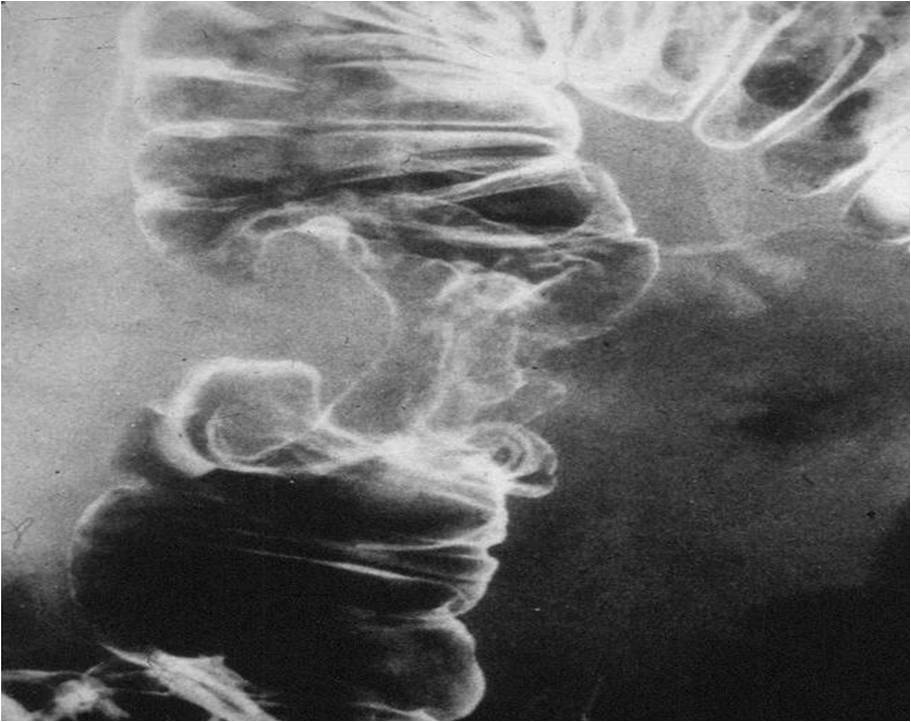

Chron’s disease

Clinical presentation: diarrhea, weight loss.

Image

Fig.22. Crohn’s disease

Radiographic findings: Most frequently luminal narrowing of the terminal ileum is detected. The wall is thickened, intramural and inter-intestinal fistulas may develop. The abdominal plain film is not suitable for identification of abdominal abscesses.